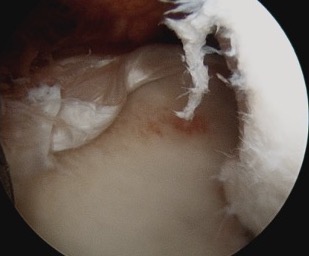

End result